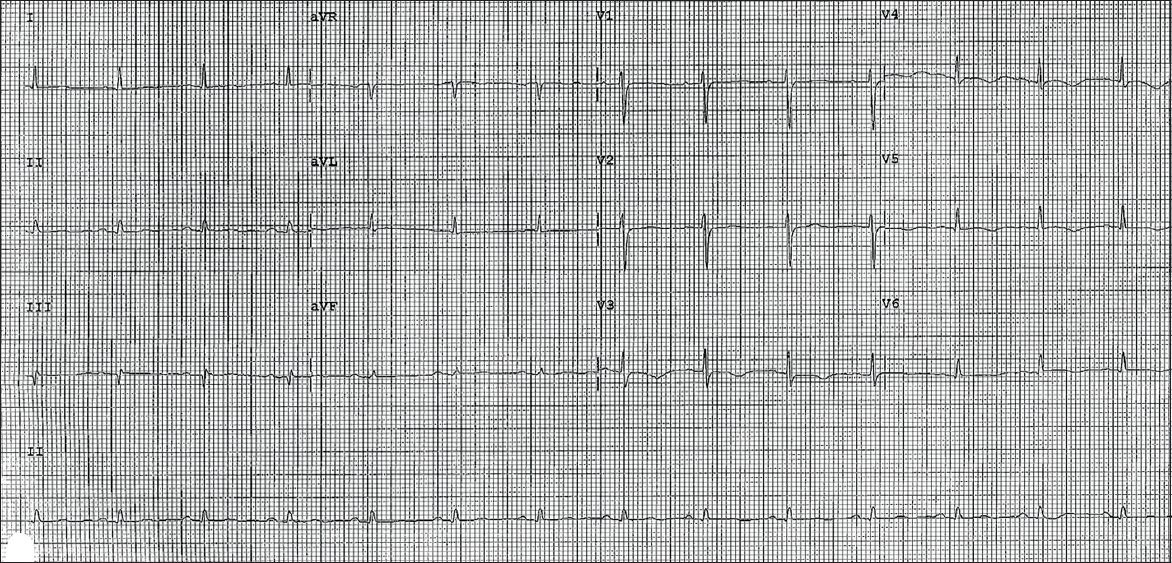

12-lead electrocardiography (ECG) performed on arrival at the emergency department showed 1 mm concave ST elevation in leads V3–6, I, II and aVF (

Fig. 1

Initial ECG shows widespread 1 mm concave ST elevations in leads V3–6, II and aVF.